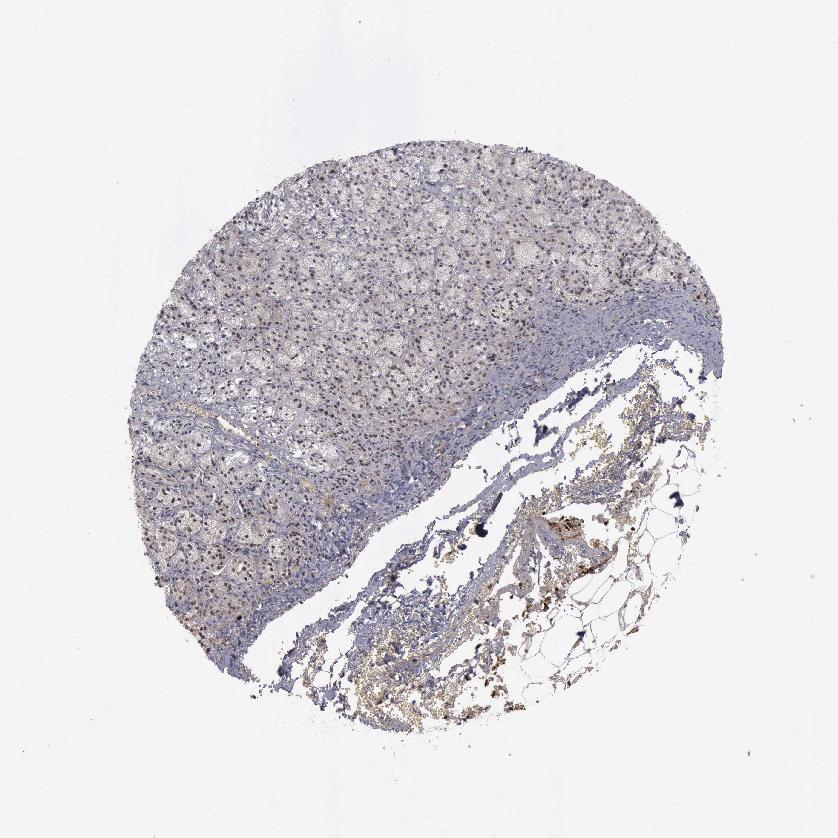

ADRENAL GLAND - Antibody stainingi

Antibody staining in the annotated cell types in the current human tissue is reported as not detected, low, medium, or high, based on conventional immunohistochemistry profiling in selected tissues. This score is based on the combination of the staining intensity and fraction of stained cells.

Each image is clickable and will lead to virtual microscopy that enables deeper exploration of all samples and also displays staining intensity scores, fraction scores and subcellular localization as well as patient and tissue information for each sample.

Antibody HPA001238Antibody HPA063909Antibody CAB000348Antibody CAB068199Antibody CAB068200Antibody CAB068201

Glandular cells Not detectedNot detectedNot detectedNot detectedNot detectedNot detected